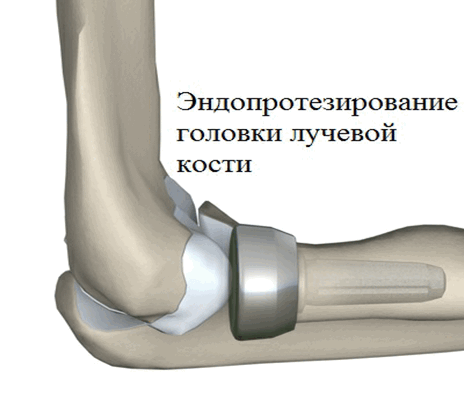

При эндопротезировании возможна замена как костей, так и их фрагментов:

- головки лучевой кости;